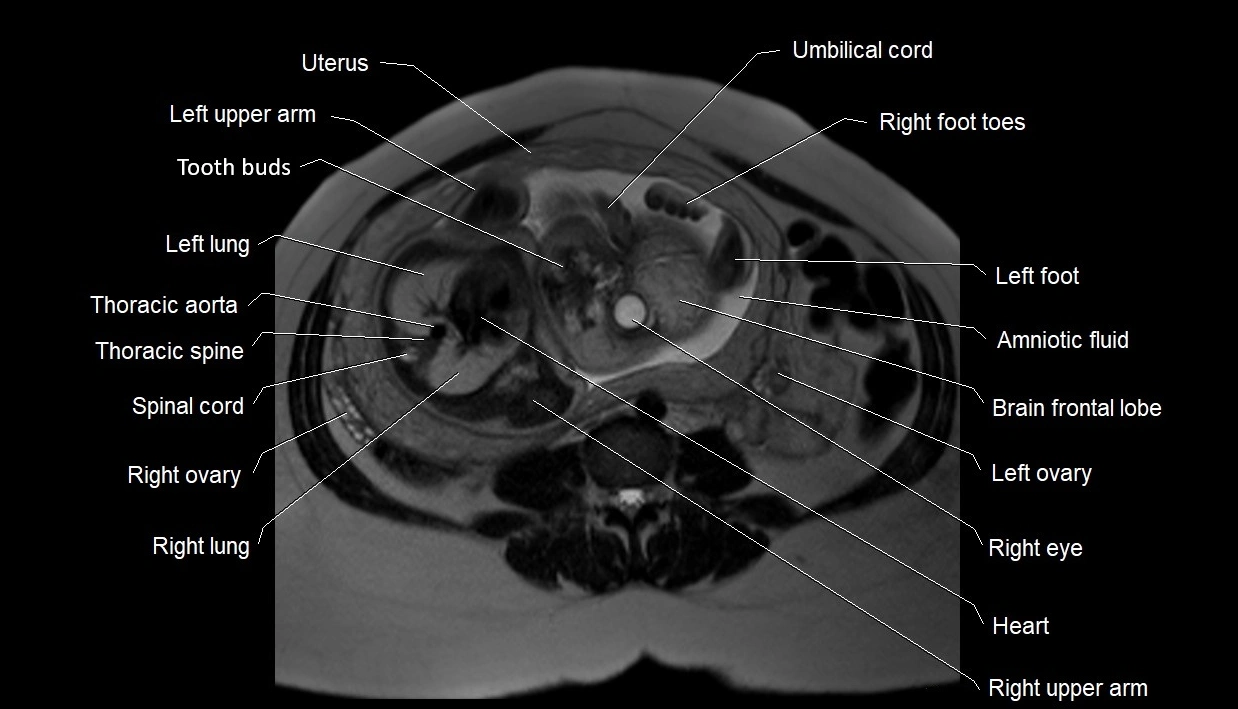

MRI Appearance

T2 HASTE (T2 GRE):

• Amniotic fluid shows very bright hyperintense signal

• Provides natural contrast against fetus and placenta

• Small particles (vernix) may appear as scattered hypointense foci within bright fluid

MRI image

image